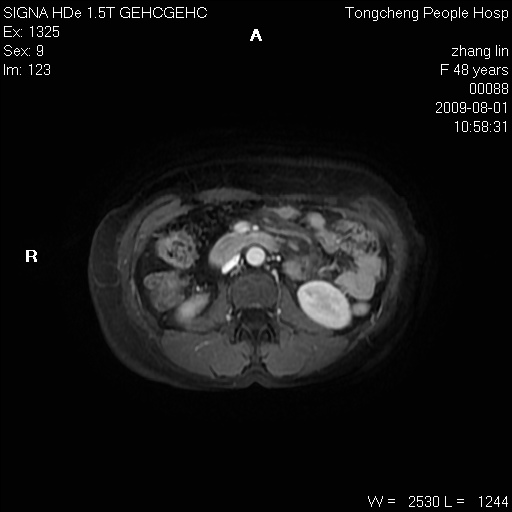

女,48岁。健康体检,彩超发现右肾占位性病变。平素健康。

临床诊断:右肾占位性病变,性质待定(囊肿?肿瘤?)。

上中腹部mr平扫+增强扫描,图像如下:

右肾上极见一类圆形病灶,t1wi呈等信号t2wi呈等高混杂信号,三期增强无强化,边界清---考虑囊肿出血。

同反相位均表现为等信号,病变无强化,考虑含蛋白的囊肿可能,弥散加权相或许有些帮助,

慢性胆囊炎